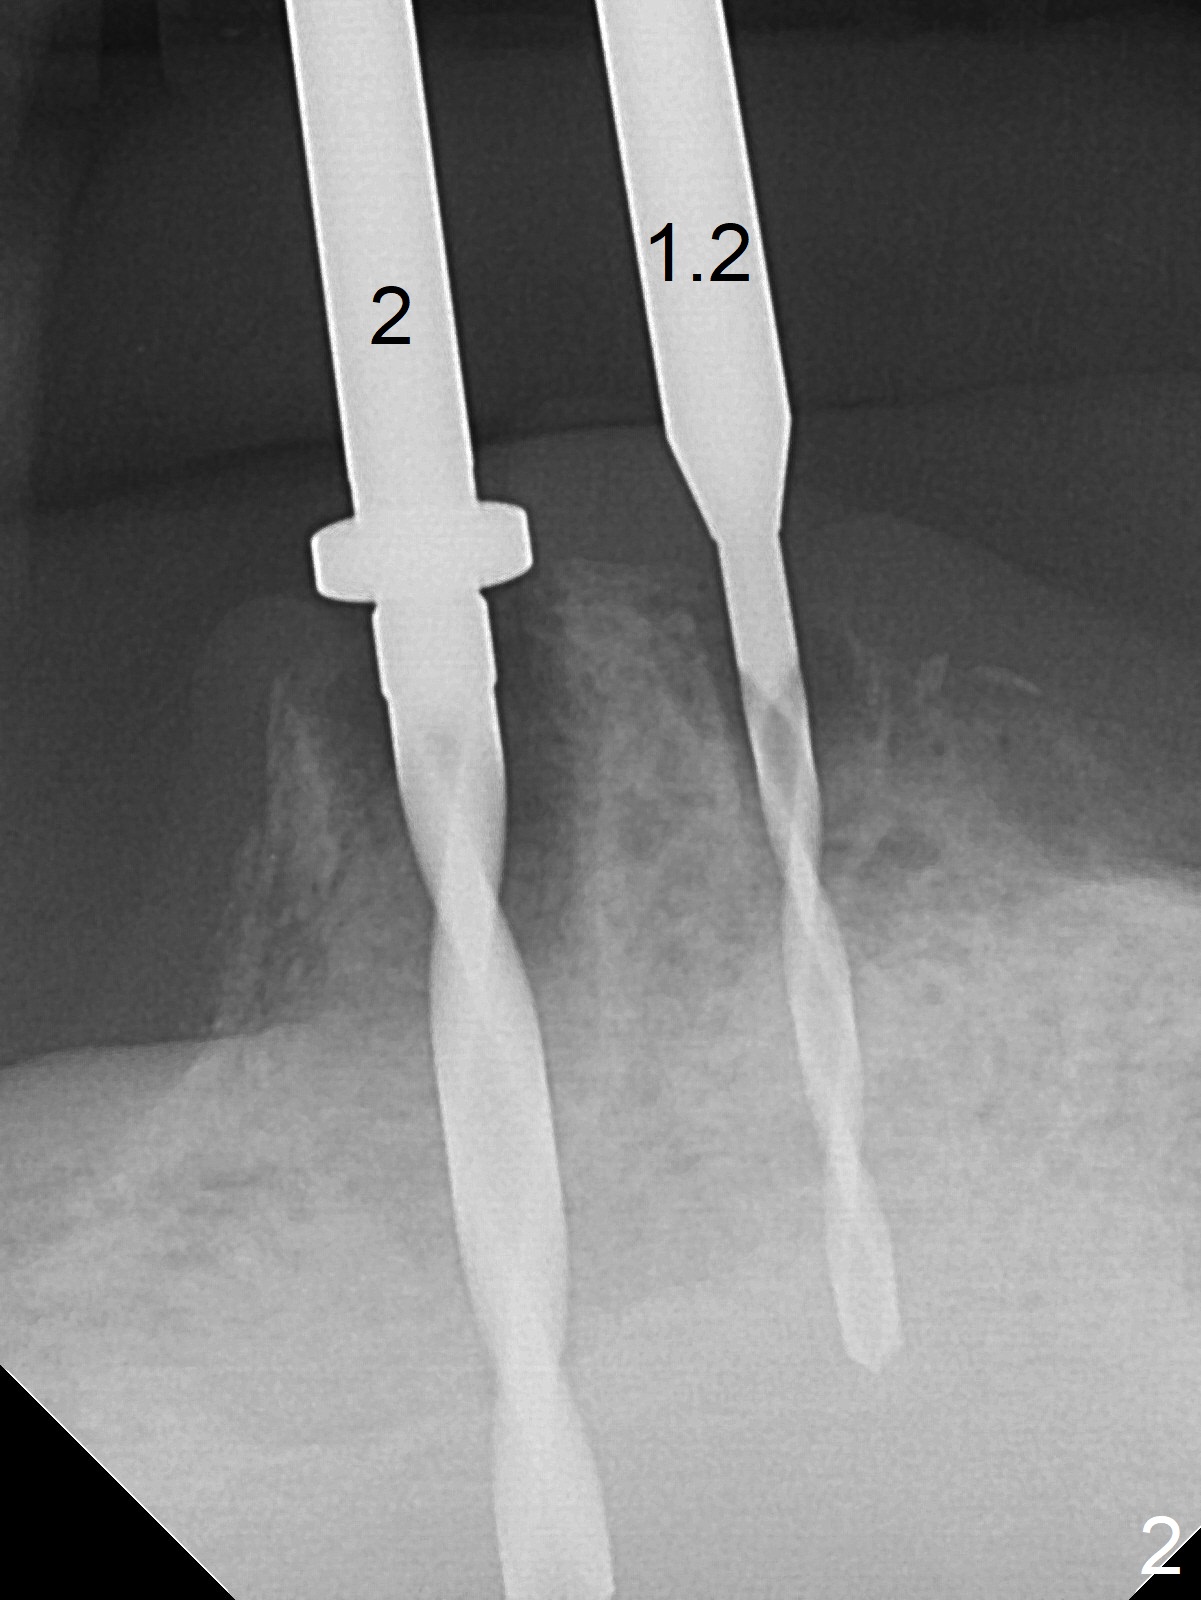

When the patient returns for #26 extraction and immediate implant and #27 RCT, it appears that the tooth #27 with subgingival margin distolingually is non-salvageable (Fig.1). She has dry mouth. Osteotomy is initiated in the lingual slope (Fig.4 red dashed line) of each socket with 1.2 and 2 mm drills for 16 and 19 mm at #26 and 27, respectively (Fig.2,3). The depth at #27 is subsequently reduced, while a 3x14(2) mm dummy implant is placed at #26 (Fig.5,6). A 3.8x13 mm implant is placed at #27 smoothly, while insertion of a 3x16(4) mm definitive implant (by mistake) has resistance (Fig.7). When the depth at #26 increases, there is feeling of perforation. The apex of the implant is truncated prior to reinsertion (Fig.8 >).

In fact the apex of the lateral incisor is also in the center of the alveolus (Fig.9 *). Osteotomy established in the lingual slope for a long distance (Fig.10,11) will perforate the lingual plate. The correct method of osteotomy is to set up in the middle of the socket and along the long axis of the alveolus with 2 fingers holding the alveolus (Fig.12 (2 circles)). The problem for this case is to use the lower RPD as a guide. With the RPD in place, the tactile sensation is lost.